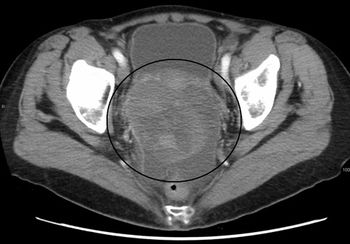

A 71-year-old woman not on hormone replacement therapy presented with uterine bleeding. Dilation and curettage revealed complex hyperplasia with atypia, focal clear-cell features, and endocervicitis. Endometrial intraepithelial carcinoma was suspected.